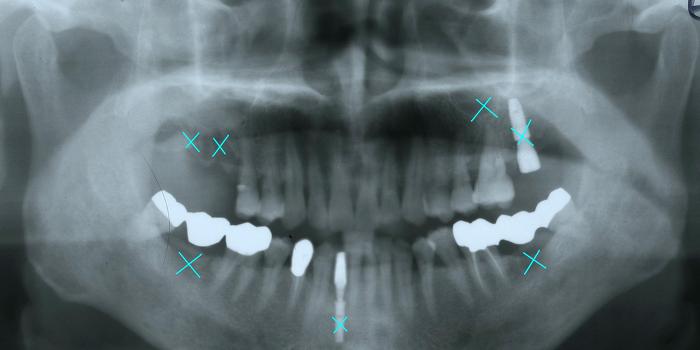

발치된 치아와 임플란트를 보여주고 있습니다.

임플란트를 해도 걱정이 되는 것은

이런 불안정한 턱 상태는 계속되는 잇몸질환, 치아 상실을 야기시키는 것이

불을 보듯 뻔하기 때문입니다.